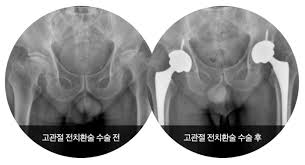

- 고관절 전치환술(Total Hip Arthroplasty, THA): 골관절염이나 류마티스 관절염, 골절 등에 널리 사용되는 방식으로, 관절 전체를 인공 관절로 교체합니다.

- 정기 검진: 엑스레이 또는 CT로 인공관절의 상태 확인